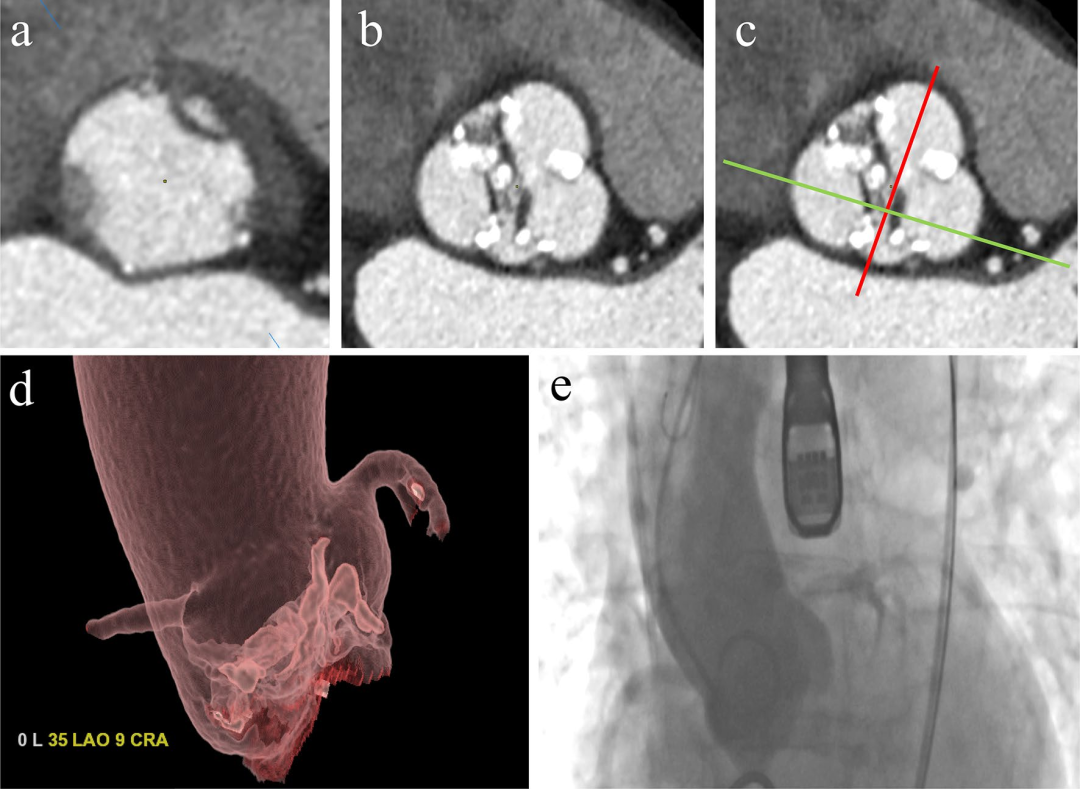

在术前 TAVI 评估中,非侵入性影像学检查在准确评估血管通路方面起着重要作用。为了最大限度地降低围术期和术后并发症的风险,准确的入路选择是手术能否进行和成功的最重要组分之一。CT比传统的单平面血管造影更准确,其能允许2D和3D重建,以最佳评估血管最小内径,血管曲折度,严重程度,动脉粥样硬化的延伸程度和形式,并识别高风险特征,包括夹层和复杂动脉粥样硬化斑块(图7)。此外,CT很容易排除先天性解剖变异(如,主动脉弓离断,牛型弓,双主动脉弓,主动脉缩窄,右或左锁骨下动脉畸变,镜像右弓)和其他主动脉异常(如动脉瘤,动脉粥样硬化/血栓形成),这可以确定最佳的血管通路。经股动脉入路仍然是所有器械的首选方法。经锁骨下动脉、颈总动脉和头臂干是TAVI的两种替代入路,而经左心室心尖入路仅适用于SAPIEN装置。经微型胸骨切开术的微创经主动脉通路是最近适用于两种装置的替代入路,其入口点在环平面上方约6厘米处。可用的设备输送系统有不同的套管尺寸,具体取决于制造商和设备的生产版本。理想情况下,原生血管的最小内径应大于所选输送套管的外径。环状的动脉粥样硬化壁钙化(或马蹄形样)、原生血管直径小和血管显著扭曲是手术并发症的危险因素,如果存在两种或两种以上特征,则必须考虑其他入路(即经心尖、经主动脉)。血管并发症是经股动脉TAVI最常见的并发症(包括瓣周反流和卒中)。外周通路的CT分析必须通过标准化方法进行,包括3D成像,曲线多平面重建和用于钙化的最大密度投影,所有测量均在血管的正交平面(横截面)中进行,以获得更准确的评估。CT对于确定假体瓣膜植入的最佳透视角度也很有价值,如图8所示。

图8:CT 确定 TAVI 手术的最佳透视角度:a 获得主动脉环的横截面(如图2中已经解释的)。b 平面向颅侧移位至主动脉瓣水平。c 所需平面 d 与主动脉瓣环(红线)和左侧和非冠状动脉瓣之间的连合线(绿线)正交。(d)所需平面的坐标(在本例中为 35 LAO 9 CRA)在 TAVI 过程中用于透视(e)